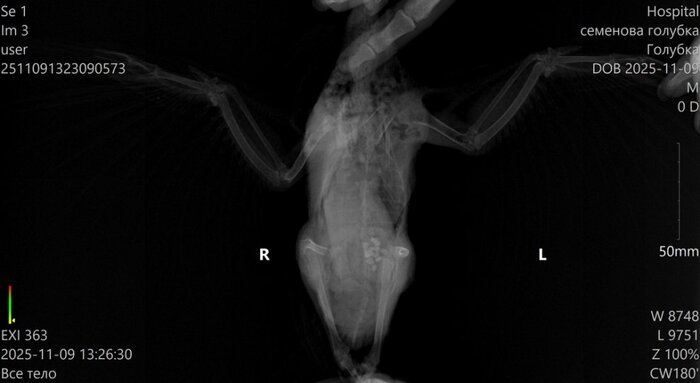

Когда приехали, ему сделали укол адреналина, чтобы стабилизировать сердце. Его состояние перестало быть таким тяжёлым, но было очевидно, что это не надолго. Сделали рентген. Почти все его лёгкие - сплошная метастаза. Ему просто нечем дышать.

Метастаза такого размера не появляется за неделю, две. Она была давно. Её можно было увидеть и оценить, переживёт ли он такую терапию. Почему никто её не увидел - я не знаю.

Перед БНЗТ мы сделали Стичу КТ (по своей инициативе, нас смутили такие низкие требования к процедуре). Это было до облучения.

На КТ не было обнаружено метастазов в лёгких, лёгкие были чистыми.

Метастазы такого размера, как на рентгене в последний день НЕ МОГУТ вырасти за неделю-две. Получается точнее будет это назвать острым патологическим процессом, произошедшим после терапии.

есть возможность, что до БНЗТ были только микроскопические метастазы, и их не могло быть видно, но даже они не способны за 12 дней заполнить лёгкие таким массивом ткани.

7 числа случилась острая дыхательная недостаточность, задыхался, пена изо рта, судороги. Когда сделали рентген, стало ясно, что лёгкие почти полностью забиты патологической тканью, газообмена не осталось, дышать просто нечем.

Т.е. чтобы поправить саму себя в своем же посте, уточняю: это была не опухоль, которая выросла,

а разрушение лёгких, произошедшее в течение тех самых 10-12 дней, когда никто не предупредил нас, что нужно делать КТ, рентген, анализы или обращаться срочно.

кт до бнзт - чистые лёгкие, метастазы размером на всё лёгкое не растут за 10 дней, значит, убил Стича

острый процесс, развившийся после БНЗТ.